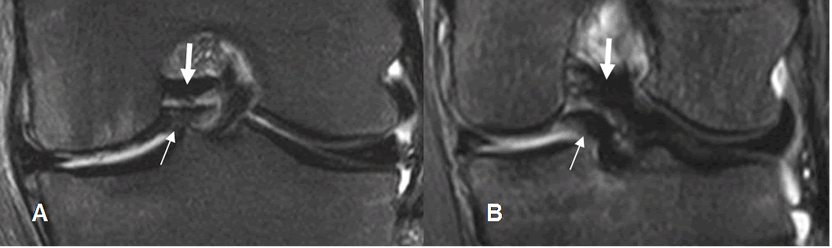

Fig 78. Ruptura meniscal en asa de cubo.

A y B: RM sagital en T2. Signo clásico del doble LCP, por ruptura en asa de cubo. LCP normal (Flecha gruesa) y menisco desplazado (Flecha delgada).

Fig 79. Ruptura meniscal en asa de cubo.

A y B: RM coronal en STIR. Fragmento meniscal ocupando la región intercondilea, por ruptura en asa de cubo. LCP normal (Flecha gruesa) y menisco desplazado (Flecha delgada).